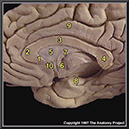

N1A5P7

21